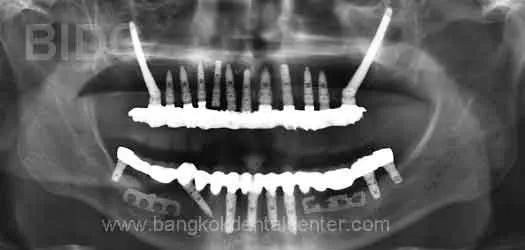

Upper Zygomatic Implants and Full Lower Bridge Implants

zygoma ferwada

Diagnoses: Poor Prognosis of Upper and Lower Teeth

Treatment : Zygoma implants and implants with hybrid fixed bridges on upper arch;

fixed bridges on implants on lower arch

Patient Country : Europe